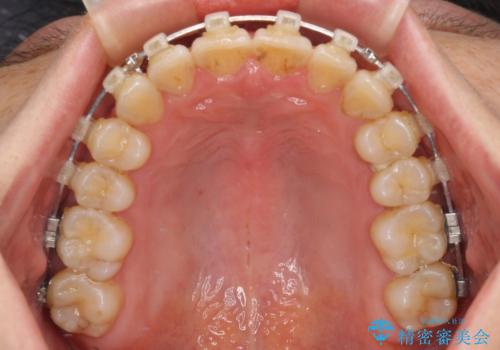

- クリアブラケット

- 治療期間

- 1年

仕事と小さいお子さんの育児に追われており、インビザラインの自己管理は続ける自信がないとのことで、ワイヤー装置による矯正治療を行うこととしました。

僅か1年間できれいに歯列を整えることができ、患者様には大変満足していただきました。